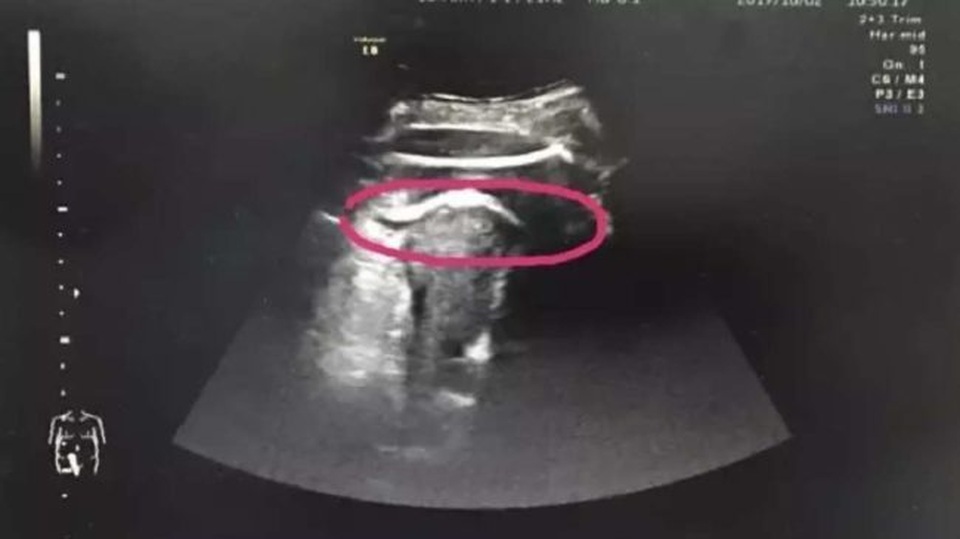

Trước khi có thai, Zhang đã làm phẫu thuật cắt bỏ khối u xơ lành tính trong tử cung. Zhang đã được đưa đi siêu âm ngay lập tức để đảm bảo rằng tử cung của cô chưa bị rách.

Thế nhưng chỉ vài phút sau, cô được đưa lên bàn mổ ngay lập tức vì các bác sĩ phát hiện ra chân của thai nhi đã đạp thủng tử cung và chui vào trong ổ bụng.